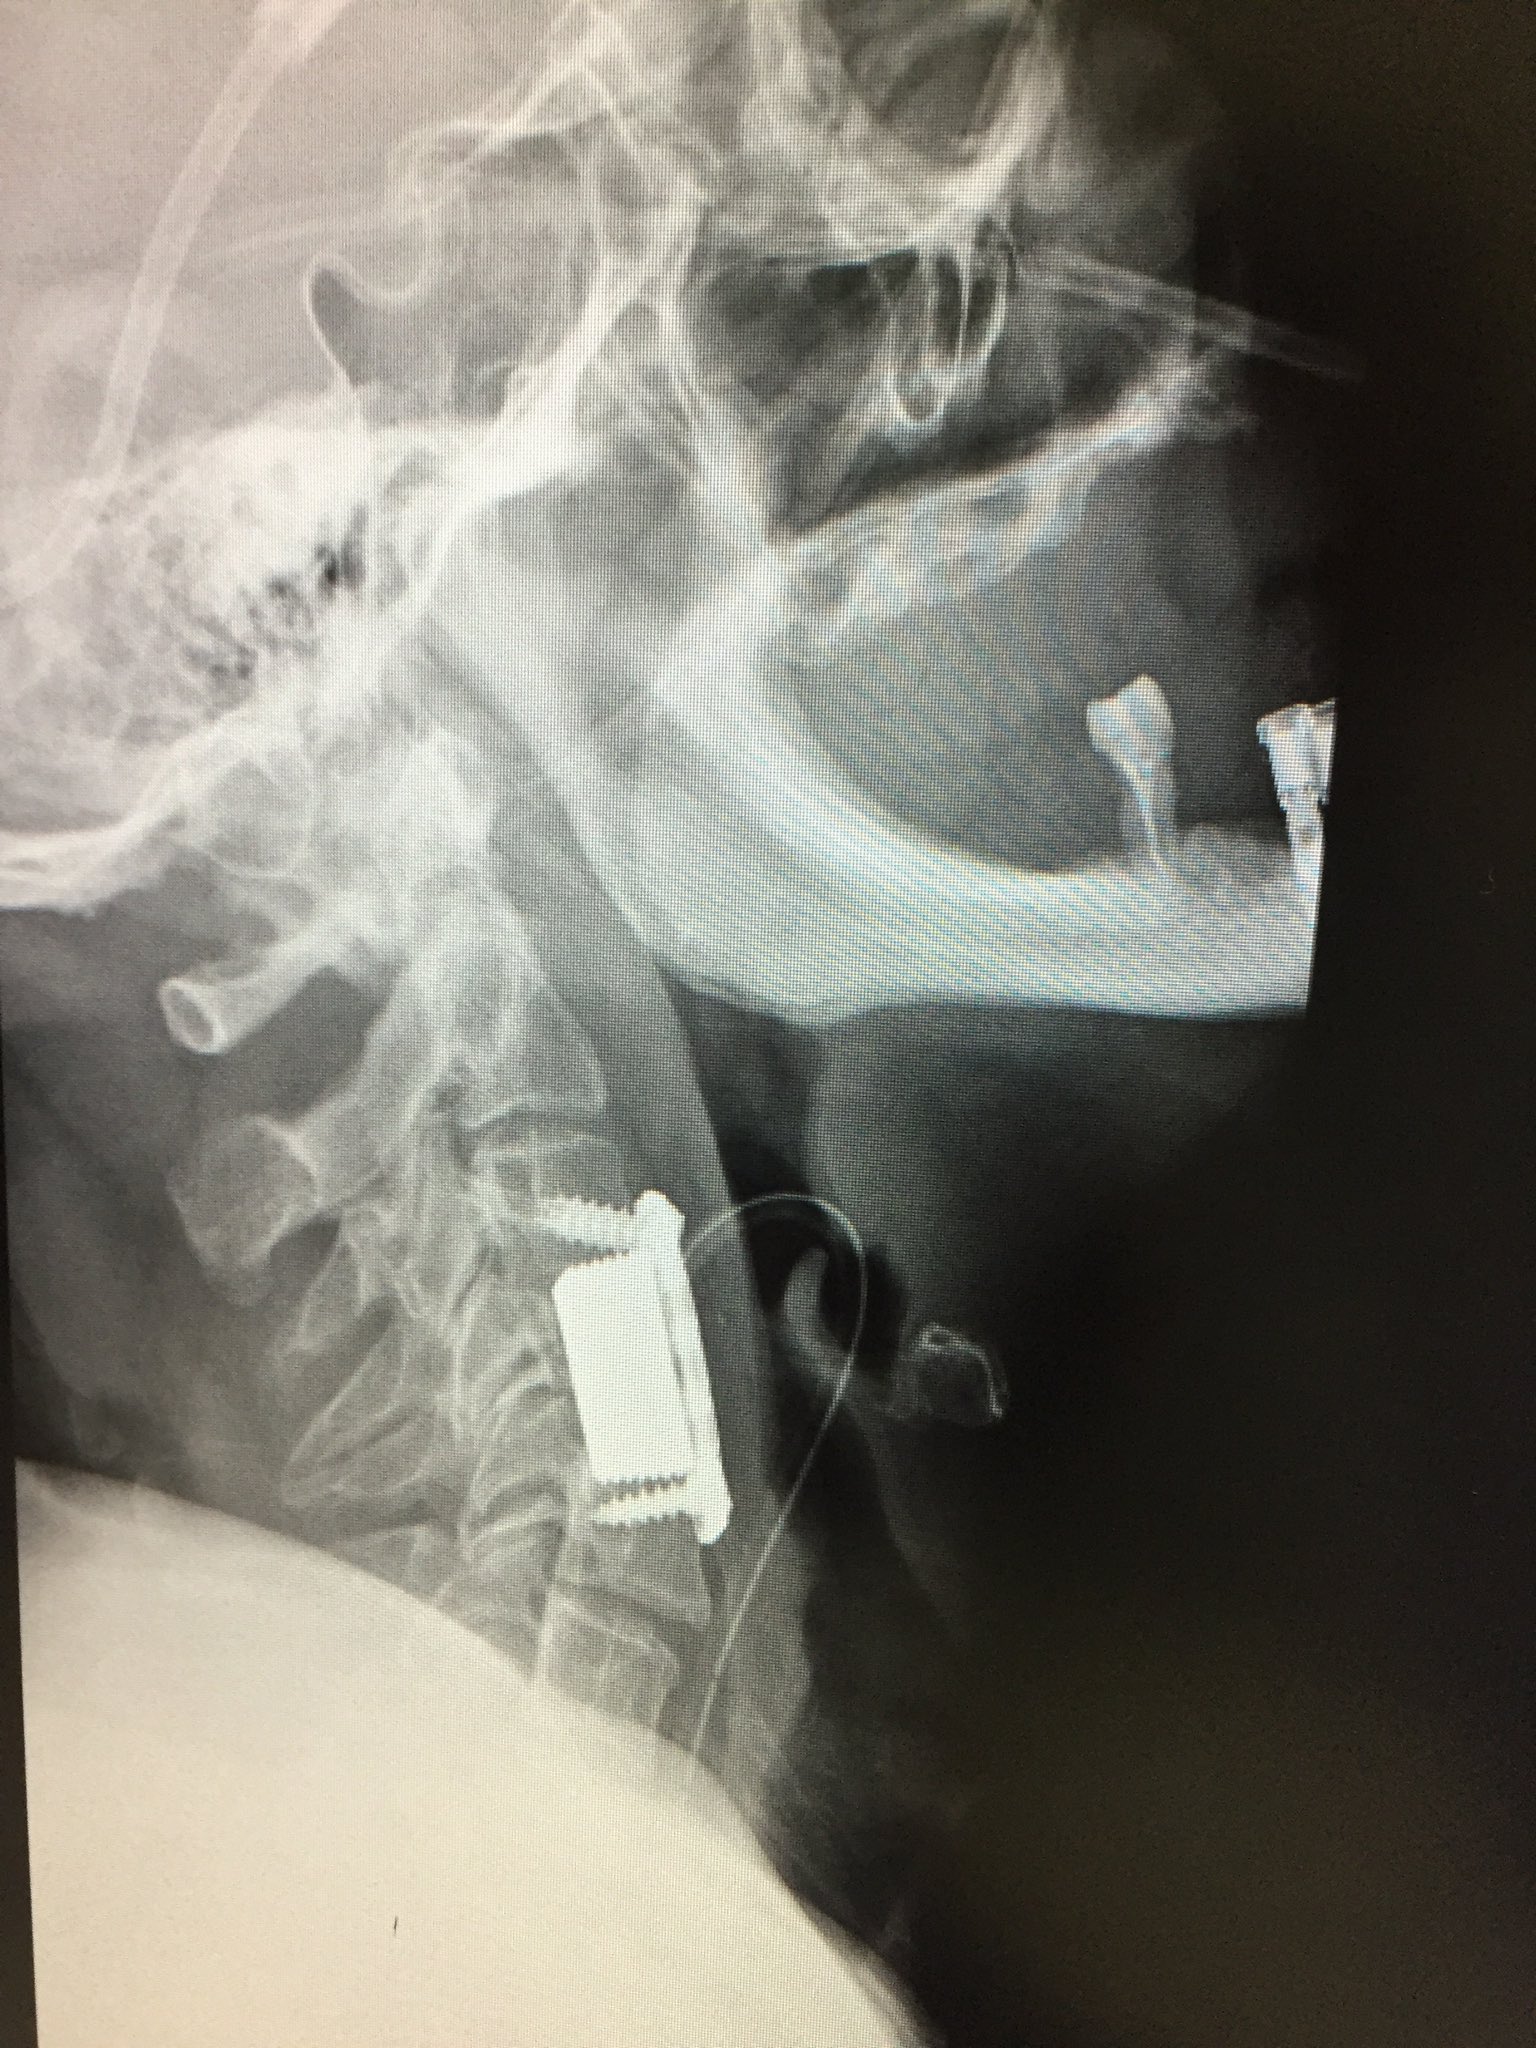

Se me rompió la columna: Artrodesis cervical. Consecuencias.

Source: semerompiolacolumna.blogspot.com